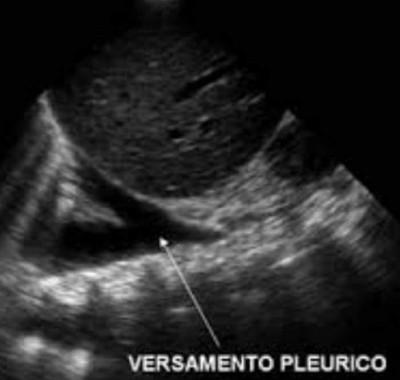

L’ecografia polmonare è una tecnica diagnostica utile a valutare malattie del polmone e della membrana che lo avvolge (pleura), nonché ad ottenere informazioni sulla presenza di versamento pleurico e pneumotorace, cioè un accumulo anomalo di aria nello spazio fra polmoni e parete toracica. In alcuni casi l’ecografia polmonare è preferibile alla radiografia per evitare l’esposizione ai raggi X.Per ottenere l’immagine del polmone si utilizza una sonda ecografica che invia ultrasuoni all’organo e converte in segnali elettrici le onde sonore che riceve di ritorno. Un computer analizza e trasforma questi segnali in immagini.